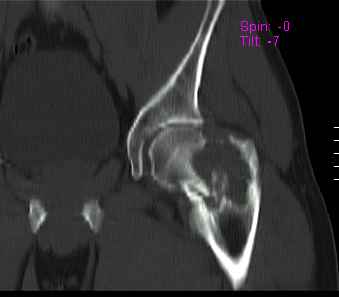

Уважаемые коллеги! Больной (1974 г.р.) травма 26.01.2009г., у пал  на

ра-боте с высоты  своего роста, доставлен  в одну из больниц

Екатеринбурга в травматологическое отделение. На рентгенограмме

выявлен патологический перелом чрезвертельной области левого бедра.

Доброкачественная опухоль (ОБК?, энхондрома?), по данным RS.

Дополнительно произведено  КТ.